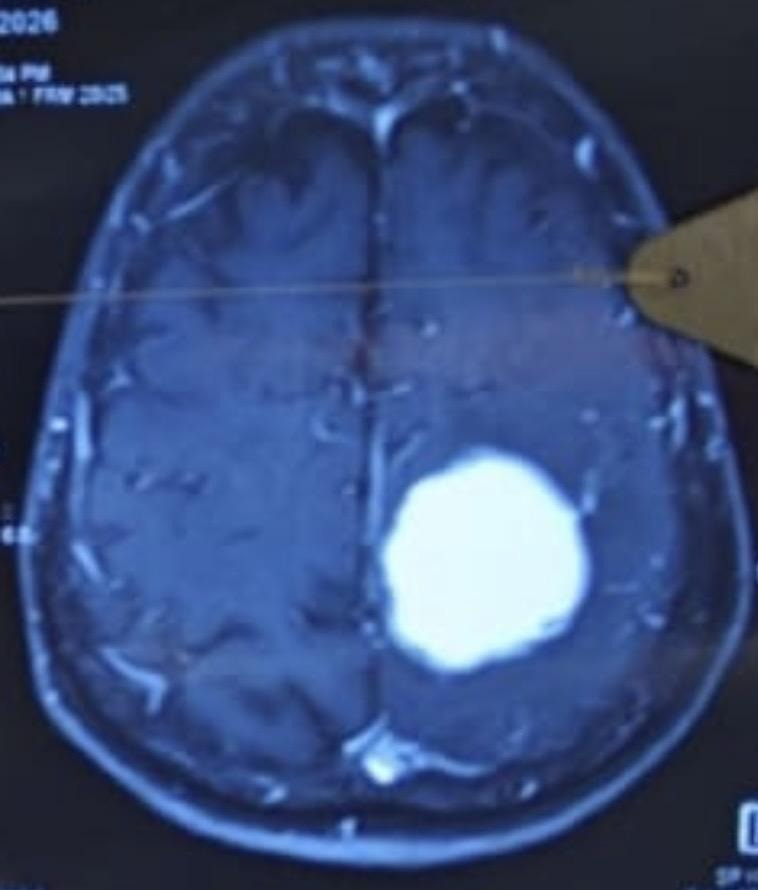

A brain tumor is the growth of abnormal cells in the brain. These may be of different types – benign, i.e., non-growing mass, and malignant, i.e., proliferative growing masses.

Neuro Oncology is the field of medicine that combines neurology and oncology, i.e. it deals with the treatment of cancers of the brain and spine.

Comprehensive diagnosis, personalised treatment plans, and multidisciplinary expertise to help you fight brain tumour with confidence and clarity